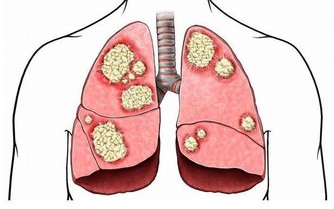

之前我寫過一篇《你覺得錢重要,還是健康重要?》的文章,看到有個朋友留言說,她曾因為晚睡,埋下病根,高考前突然爆發,花掉了家裡兩萬塊錢,住院半個月。進醫院的第一天做了很多檢查,期間還做了手術,直到現在都還需要進行定期檢查。